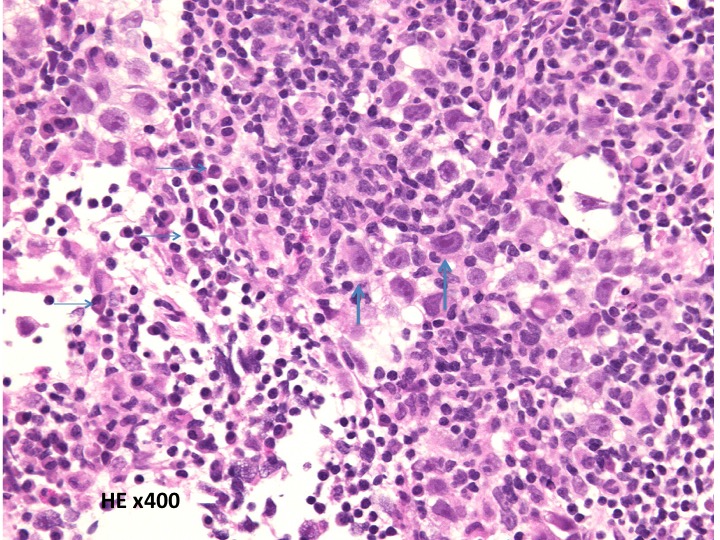

病理診断は困難ではありません。左側の写真のように,多くの場合にHE染色でtwo-cell patternと呼ばれる, 大型の腫瘍細胞と小型のリンパ球 (T cells) 浸潤の特徴的な病理像で診断がつきます。大型の腫瘍細胞は楕円形の大きな核に大きな核小体が特徴です。

弱拡像です。類円形で大型の核を有するgerm cell (胚細胞)類似の細胞と小型のリンパ球からなる腫瘍で、two cell patternと呼ばれています。

大型のgerm cell類似の細胞 (germ cellと呼ぶ)では腫大した核小体が明瞭にみられます(太い矢印)。小型の細胞の中にはplasma cell (細い矢印)も見られます。